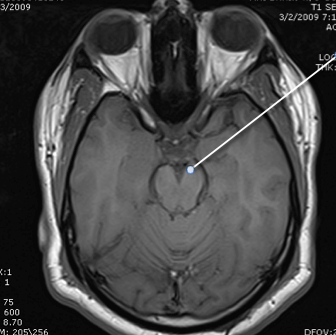

medulla

cerebellum

4th ventricle